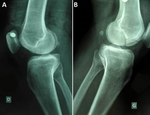

Hoffa fracture Albert Hoffa Hoffa fracture of medial unicondylar and bilateral in a man a rare case 2015 P03.png